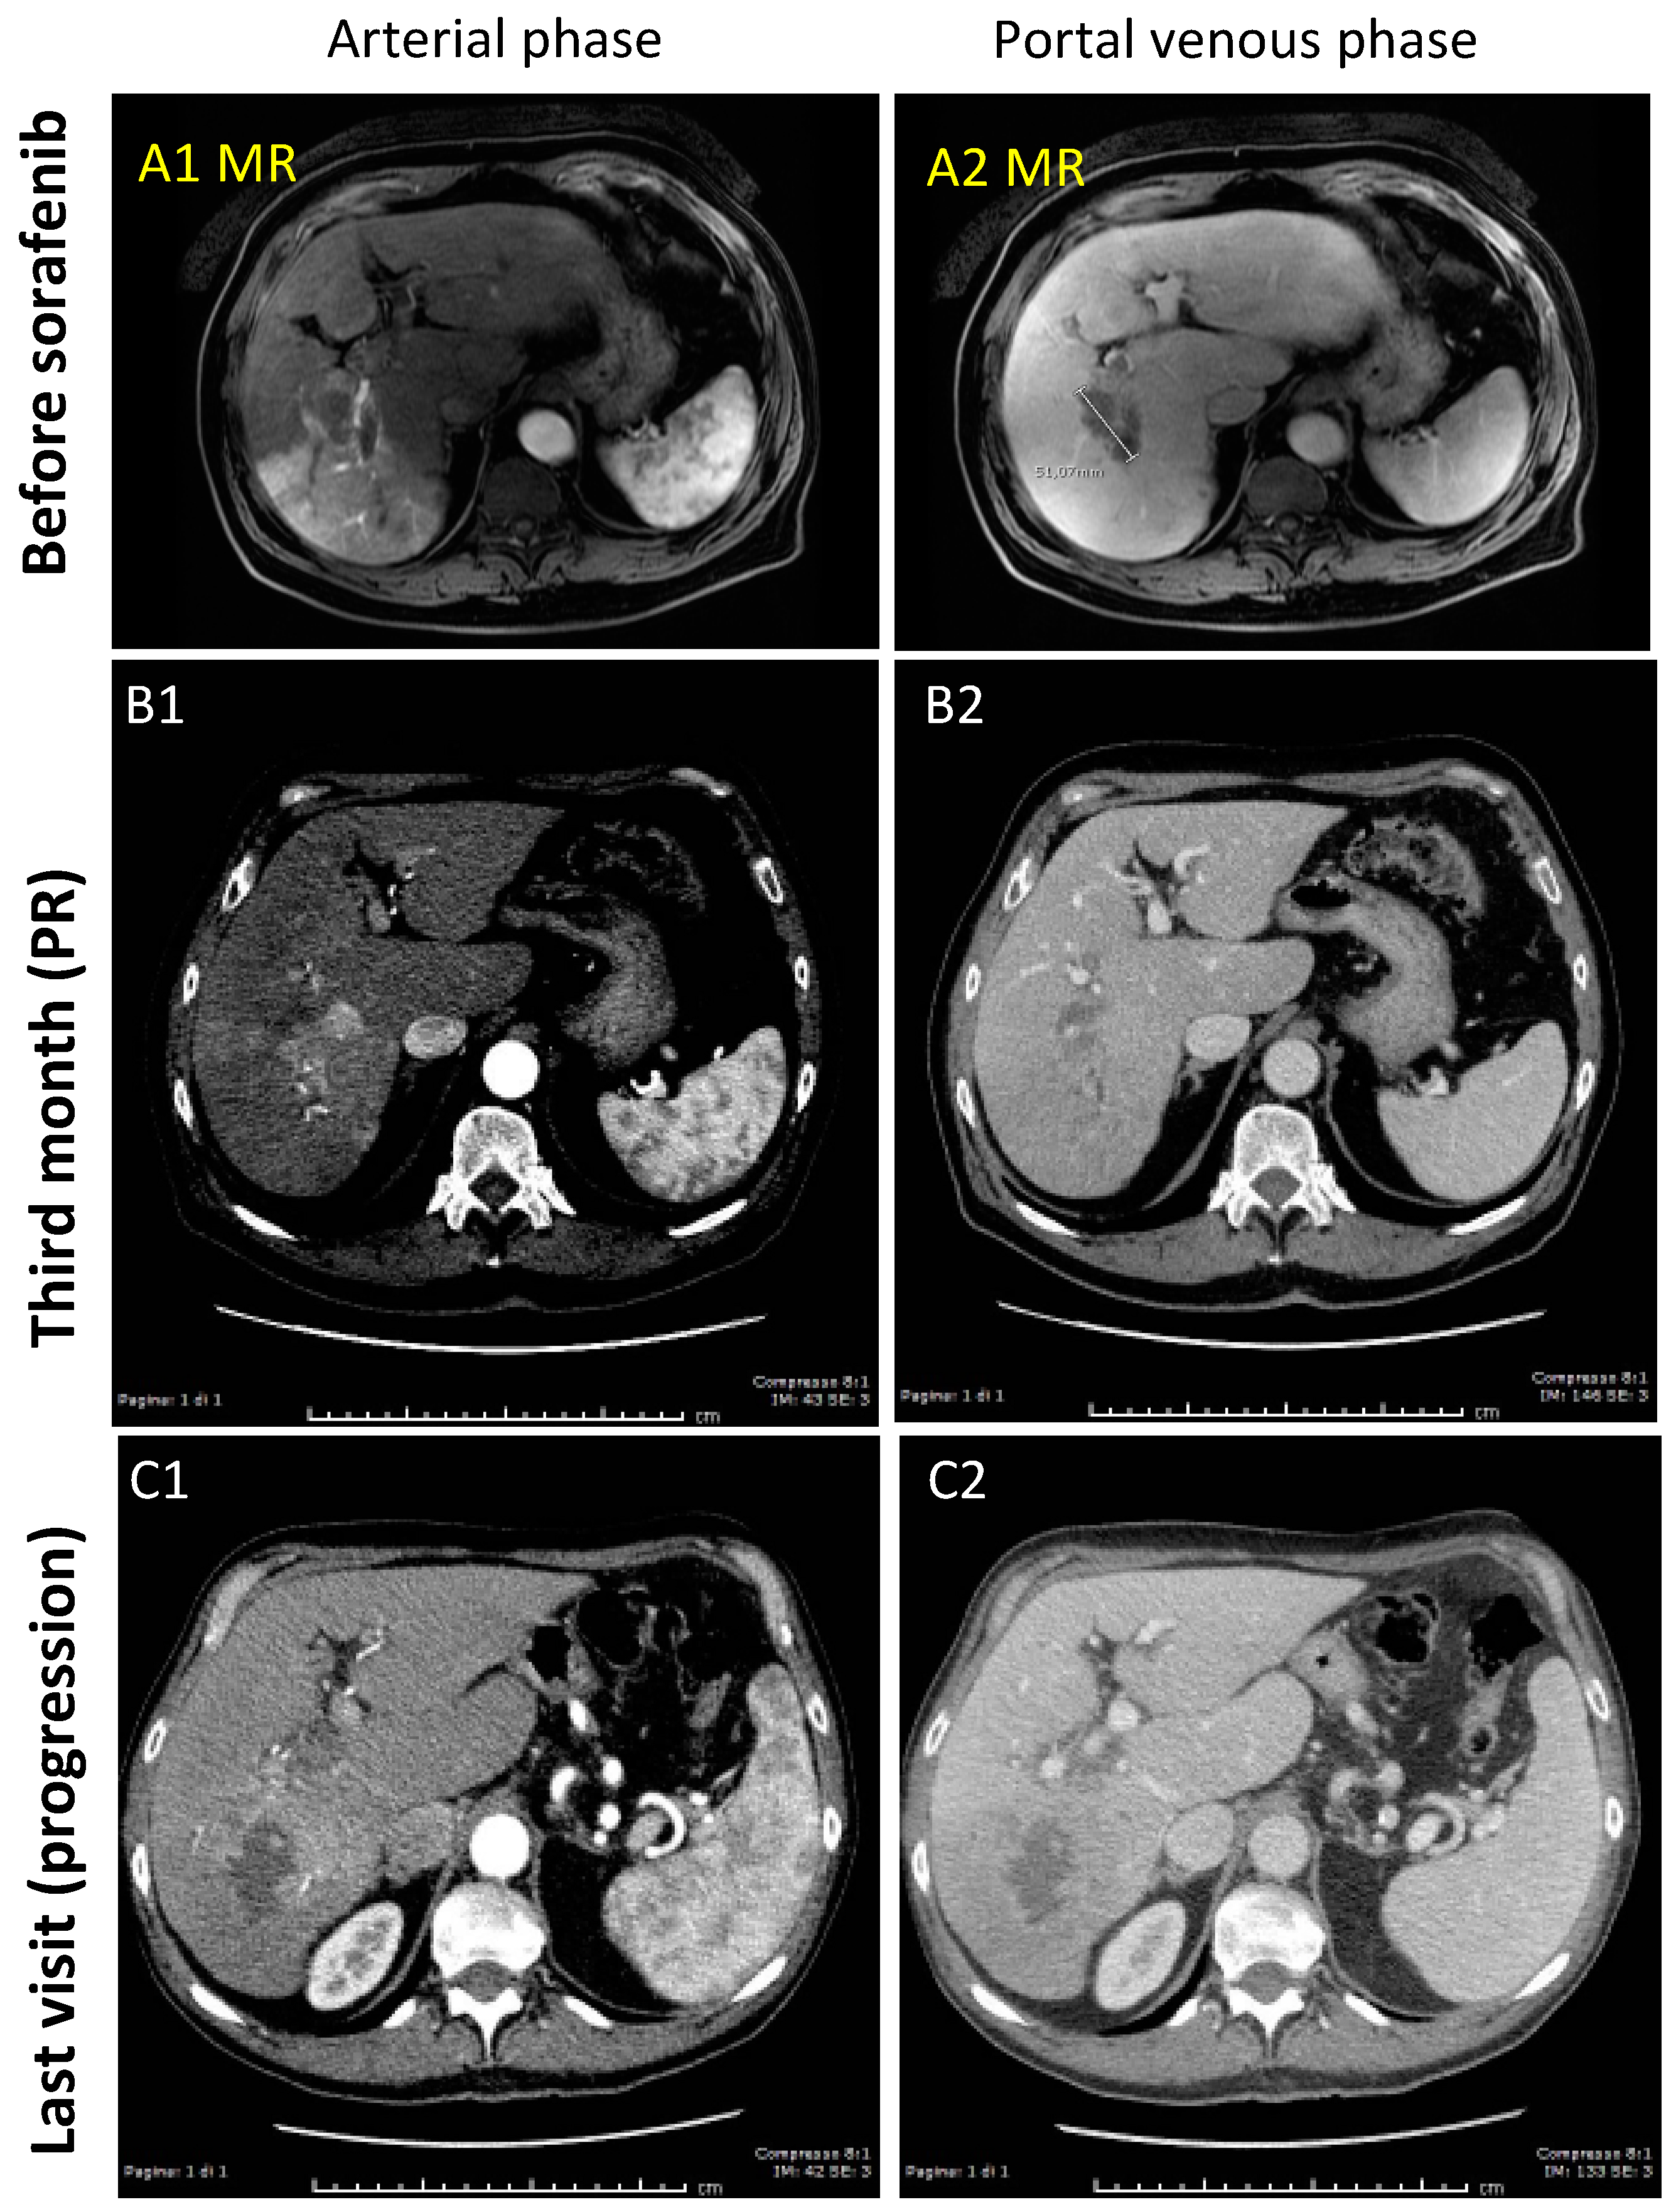

3.1.2. Case-2 (PR to Sorafenib)

| HCC volume (cm3) | 139 | 32 | 52.2 | 6.4 | 24.5 | 6.1 | 200 | 89 | 29.1 | 116 |

| Target Response * | CR | PR | PR | CR | CR | CR | SD | SD | PD | PD |

| Overall Response * | CR | PD | PR | CR ** | PD | PD | PD | PD | PD | PD |